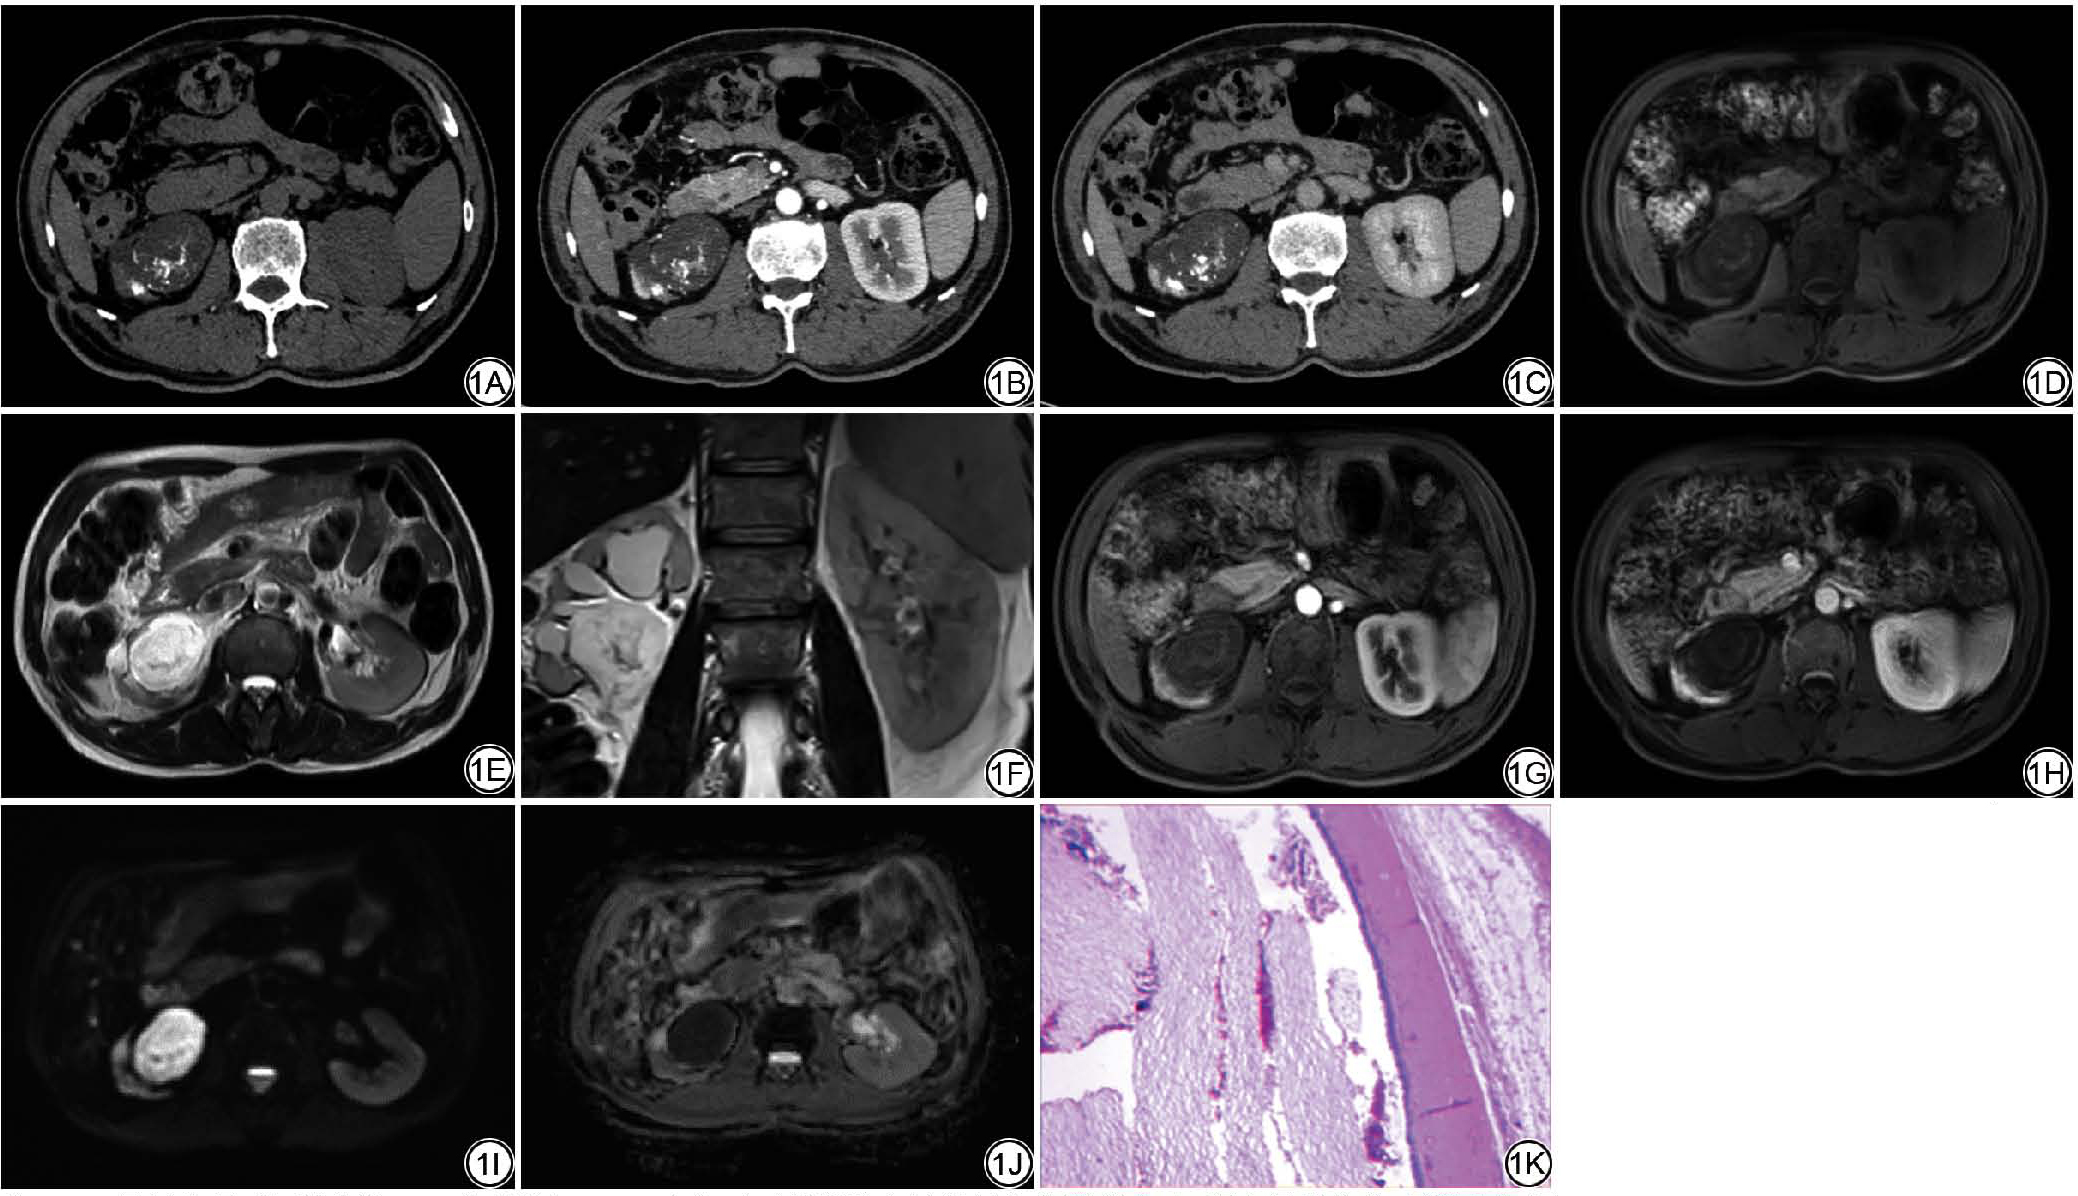

患者男,64岁,因体检发现右肾占位1周就诊,无腰痛、尿频、尿急及肉眼血尿等临床症状。体格检查和实验室检查均未见明显异常。于2019年12月20日收住我院泌尿外科。计算机断层成像尿路造影(computed tomography urography, CTU)(图1A~1C)示:平扫示右肾盂类圆形混杂密度肿块,大小约4.5 cm×4.4 cm×4.9 cm,边界清晰,病灶主体呈囊性低密度,平扫CT值约23 HU,其内见无定型样钙化灶,增强扫描未见强化;肾盏积水扩张,肾下极实质萎缩;肾周未见明确肿大淋巴结,双肾动静脉及下腔静脉未见明确受侵征象。CT诊断:右肾盂病变,考虑间叶源性肿瘤伴钙化,R.E.N.A.L.评分系统[R (radius); E (exophytic/endophytic properties); N (nearness of tumour to the collecting system or sinus); A (anterior/posterior descriptor); L (location relative to polar lines)]评分为9A分(2+2+3+A+3)。磁共振尿路成像(magnetic resonance urography, MRU)(图1D~1J)示:右肾盂区类圆形占位,T1加权成像(T1-weighted imaging, T1WI)呈低信号,T2加权成像(T2-weighted imaging, T2WI)呈高信号,T1WI见少量絮状高信号,T2WI见多发斑点状低信号,弥散加权成像(diffusion-weighted imaging, DWI)呈高信号(b=800 s/mm2),表观扩散系数(apparent diffusion coefficient, ADC呈低信号,边界清晰,增强扫描未见强化;肾盏积水扩张。MRI诊断:右肾盂囊实性占位伴钙化、出血。患者遂行腹腔镜下右肾切除术。术中所见:右肾盂囊性肿块,大小约5.0 cm×4.5 cm×4.5 cm,内含豆渣样物。术后病理(图1K)诊断:肾脏成熟性囊性畸胎瘤。囊壁内衬复层角化鳞状上皮,囊内见角化物及少量脂肪组织。术后65个月电话随访,患者状况良好,外院复查未见复发及转移。

图1  男,64岁,右肾窦成熟性囊性畸胎瘤。1A:CT平扫示右肾盂类圆形混杂低密度影,大小约4.5 cm×4.4 cm×4.9 cm,边界清楚,内见无定型样钙化影;1B~1C:CT增强扫描未见强化;1D:T1WI呈低信号,内见斑片状低信号及絮状高信号;1E~1F:T2WI呈高信号,内见斑片状低信号,肾盏积水扩张;1G~1H:MRI增强未见强化;1I ~1J:DWI(b=800 s/mm2)呈高信号,ADC呈低信号,边界清晰;1K:病理图(HE ×100)镜下可见囊壁内衬复层角化鳞状上皮、囊内见角化物,囊肿周围见少量脂肪组织。DWI:弥散加权成像。

Fig. 1  Male, 64 years old, mature cystic teratoma of the right renal sinus. 1A: Unenhanced CT scan shows a roundish, mixed low-density lesion in the right renal pelvis, measuring approximately 4.5 cm × 4.4 cm × 4.9 cm, with well-defined margins, amorphous calcification is visible inside; 1B-1C: Contrast-enhanced CT scan reveals no enhancement; 1D: T1-weighted MRI demonstrates hypointense signal intensity with patchy hypointense and flocculent hyperintense signals; 1E-1F: T2-weighted MRI demonstrates hyperintense signal with patchy hypointense signals, hydronephrosis with caliceal ectasia; 1G-1H: Contrast-enhanced MRI exhibits no enhancement; 1I-1J: DWI (b = 800 s/mm2) shows hyperintense signal, ADC shows hypointense signal, with clear boundaries; 1K: Histopathology (HE × 100), reveals a cyst wall lined by stratified keratinized squamous epithelium, and the cyst contains keratinized material, a small amount of adipose tissue is observed around the cyst. DWI: diffusion-weighted imaging.